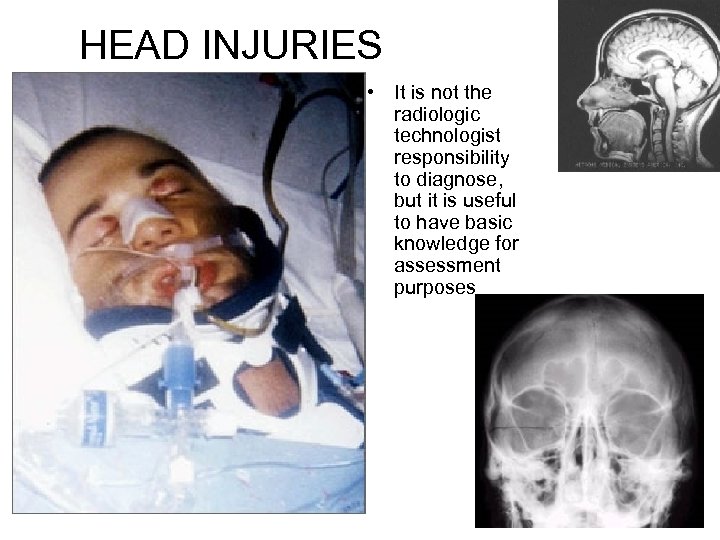

HEAD INJURIES • It is not the radiologic technologist responsibility to diagnose, but it is useful to have basic knowledge for assessment purposes

HEAD INJURIES • It is not the radiologic technologist responsibility to diagnose, but it is useful to have basic knowledge for assessment purposes